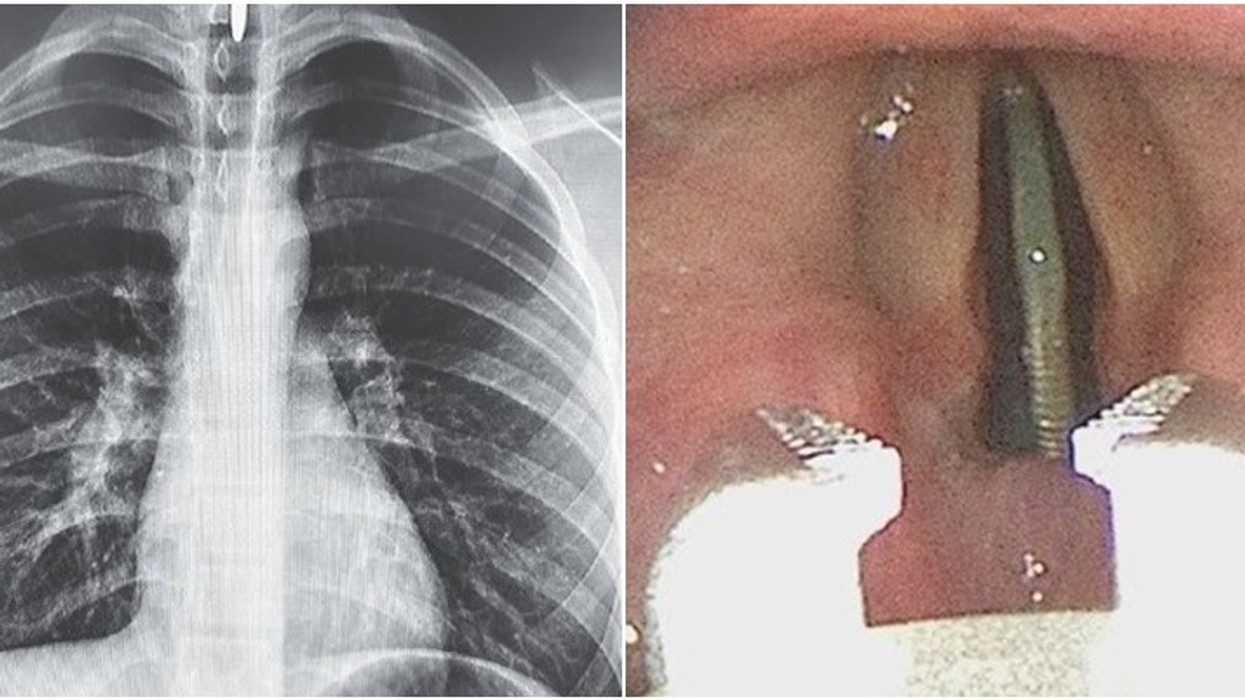

Megjithatë, pas kryerjes së një skanimi me rreze X të gjoksit dhe qafës, mjekët e kuptuan menjëherë situatën e vështirë, pasi monedha metalike kishte ngecur në një pozicion vertikal midis kordave të zërit dhe mund t'i dëmtonte ato nëse lihej për një kohë të gjatë atje.

Fotot e marra në mënyrë endoskopike tregojnë objektin metalik të ulur në subglotis si në një automat.